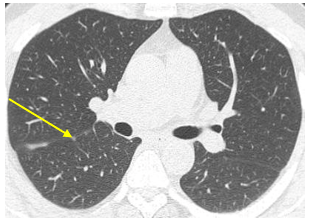

Chụp cắt lớp vi tính lồng ngực: Hình ảnh các nốt kính mờ rãnh liên thùy và màng phổi phải. Đám dải xẹp phổi thùy giữa phổi phải

Hình 9: Hình ảnh cắt lớp vi tính lồng ngực sau 15 tháng điều trị

Chụp cắt lớp vi tính ổ bụng: Không phát hiện tổn thương

Siêu âm hạch cổ 21/10/2024:  Hình ảnh siêu âm hạch vùng cổ không thấy bất thường.

Đánh giá: Bệnh đáp ứng 1 phần

Điều trị tiếp: Alectinib 600mg/lần x 2 lần/ngày, uống trong bữa ăn

Sau 20 tháng điều trị: đánh giá bệnh đáp ứng 1 phần. Hiện tại bệnh nhân không có triệu chứng cơ năng trên lâm sàng, tăng 2kg so với trước điều trị. Tác dụng phụ táo bón nhẹ.

Chất chỉ điểm u CEA, Cyfra 21-1 trong giới hạn bình thường.

Công thức máu, sinh hoá máu trong giới hạn bình thường.

Đáp ứng hình ảnh tốt, không còn tổn thương hoạt động rõ. Không xuất hiện các tổn thương mới tại phổi hay tại các cơ quan khác

Bệnh nhân tiếp tục được điều trị duy trì Alectinib 600mg/lần x 2 lần/ngày, uống trong bữa ăn.